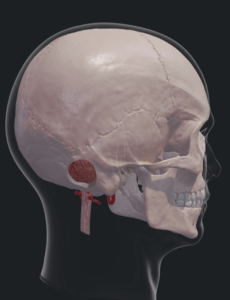

Το ενδοσκόπιο βρίσκει εφαρμογή στην χειρουργική της γεφυροπαρεγκεφαλιδικής γωνίας, είτε πρόκειται για κάποιον όγκο, όπως ακουστικό νευρίνωμα, μηνιγγίωμα ή λοιπό καλοήθη ή κακοήθη όγκο ή πρόκειται για επέμβαση νευραλγίας τριδύμου. Μέσω της οπισθιοσιγμοειδούς προσπέλασης (Εικ. 5) εισέρχεται το ενδοσκόπιο και παρέχει εξαιρετική απεικόνιση. Στο βίντεο 2 φαίνονται οι κατώτερες εγκεφαλικές συζυγίες (κρανιακά νεύρα ΙΧ μέχρι ΧΙ), κρίσιμες αγγειακές δομές και το ακουστικό νευρίνωμα.